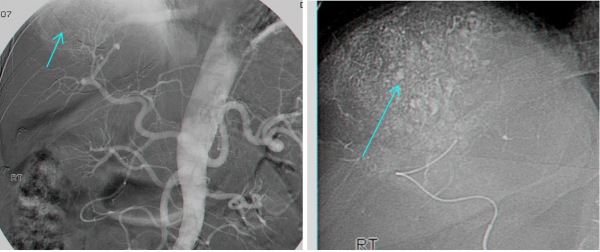

- ליפיודול הוא חומר שומני שעליו חיברו חומר ניגוד והוא נקלט היטב בשאתות מסוג HCC. יתרונו הוא בכך שהוא נשאר הרבה זמן בשאת ולכן ניתן להדגמה שוב ושוב בלא צורך להזריק חומר ניגוד. הזרקת ליפיודול יכולה לעזור לנו באבחון של שאתות בקטרים קטנים של מספר מ"מ (תצלום 35.10).

| תצלום 35.10: הדגמת השאת בכבד לאחר הזרקת ליפיודול הנקלט בשאת ונשאר בה ולכן מאפשר מעקב ממושך אחר הנגעים בכבד. | |

|---|---|

גישה טיפולית אחרת בחולים שלא ניתן לכרות בהם את השאת, היא קשירה של עורק הכבד המספק העיקרי של דם לשאת, או אמבוליזציה של כלי הדם של השאת באמצעים שונים. שיטת האמבוליזציה נקראת גם Transcatheter arterial chemoembolization (TACE) שבה מחדירים צנתר לאחד הענפים של עורק הכבד שמזין את השאת ודרכו מזריקים חומר מטרש כמו גלפום מעורב בחומר ניגוד (רדיואופקי) בעיקר ליפיודול וחומר ציטוטוקסי המקובל Cisplatin. התוצאות המדווחות אינן שונות מהתוצאות של כל טיפול תומך אחר (תצלום 36.10).